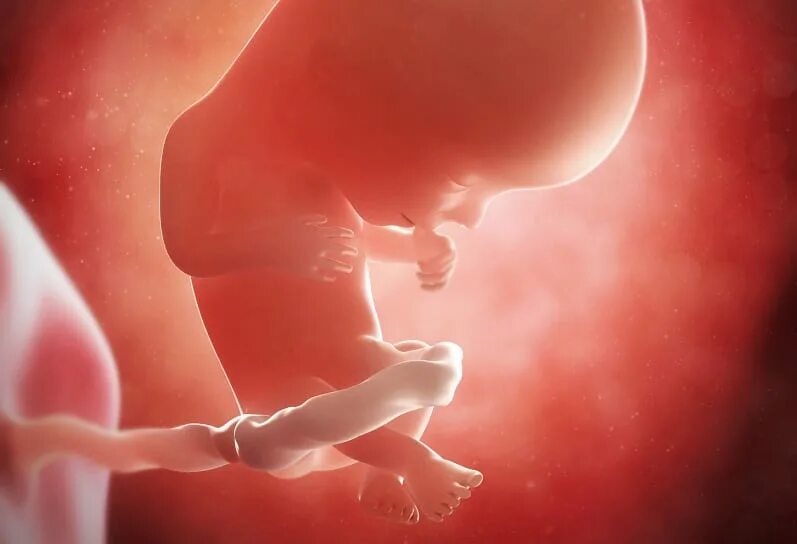

14 неделя ощущение